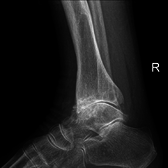

Diagnosis is made with reasonable certainty based on history and clinical examination.[42][43] X-rays may confirm the diagnosis. The typical changes seen on X-ray include: joint space narrowing, subchondral sclerosis (increased bone formation around the joint), subchondral cyst formation, and osteophytes.[44] Plain films may not correlate with the findings on physical examination or with the degree of pain.[45] Usually other imaging techniques are not necessary to clinically diagnose OA.

Severe osteoarthritis and osteopenia of the carpal joint and 1st carpometacarpel joint.